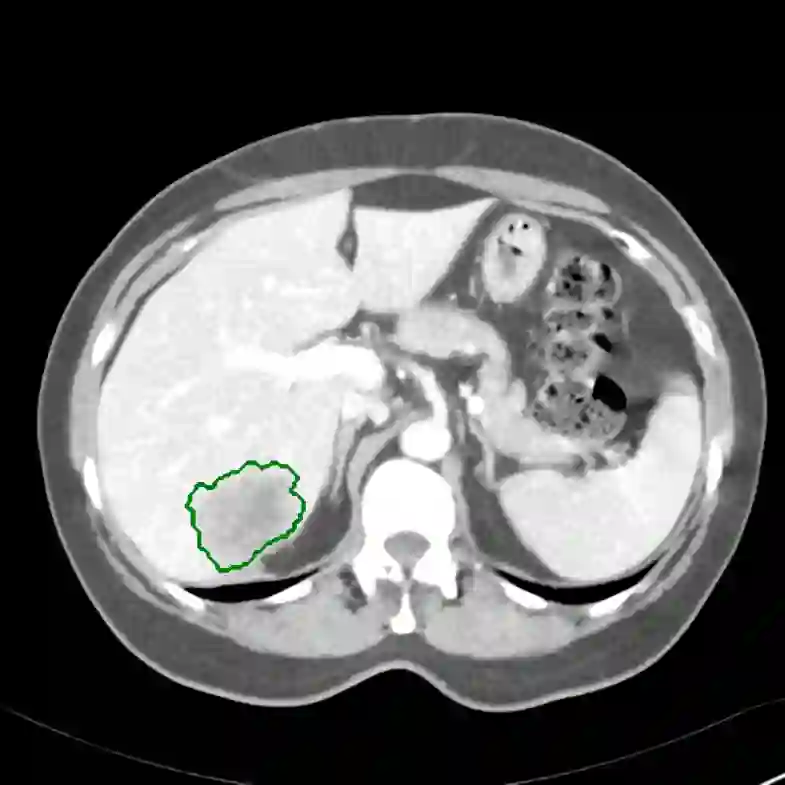

Radiomics uses quantitative medical imaging features to predict clinical outcomes. Currently, in a new clinical application, finding the optimal radiomics method out of the wide range of available options has to be done manually through a heuristic trial-and-error process. In this study we propose a framework for automatically optimizing the construction of radiomics workflows per application. To this end, we formulate radiomics as a modular workflow and include a large collection of common algorithms for each component. To optimize the workflow per application, we employ automated machine learning using a random search and ensembling. We evaluate our method in twelve different clinical applications, resulting in the following area under the curves: 1) liposarcoma (0.83); 2) desmoid-type fibromatosis (0.82); 3) primary liver tumors (0.80); 4) gastrointestinal stromal tumors (0.77); 5) colorectal liver metastases (0.61); 6) melanoma metastases (0.45); 7) hepatocellular carcinoma (0.75); 8) mesenteric fibrosis (0.80); 9) prostate cancer (0.72); 10) glioma (0.71); 11) Alzheimer's disease (0.87); and 12) head and neck cancer (0.84). We show that our framework has a competitive performance compared human experts, outperforms a radiomics baseline, and performs similar or superior to Bayesian optimization and more advanced ensemble approaches. Concluding, our method fully automatically optimizes the construction of radiomics workflows, thereby streamlining the search for radiomics biomarkers in new applications. To facilitate reproducibility and future research, we publicly release six datasets, the software implementation of our framework, and the code to reproduce this study.